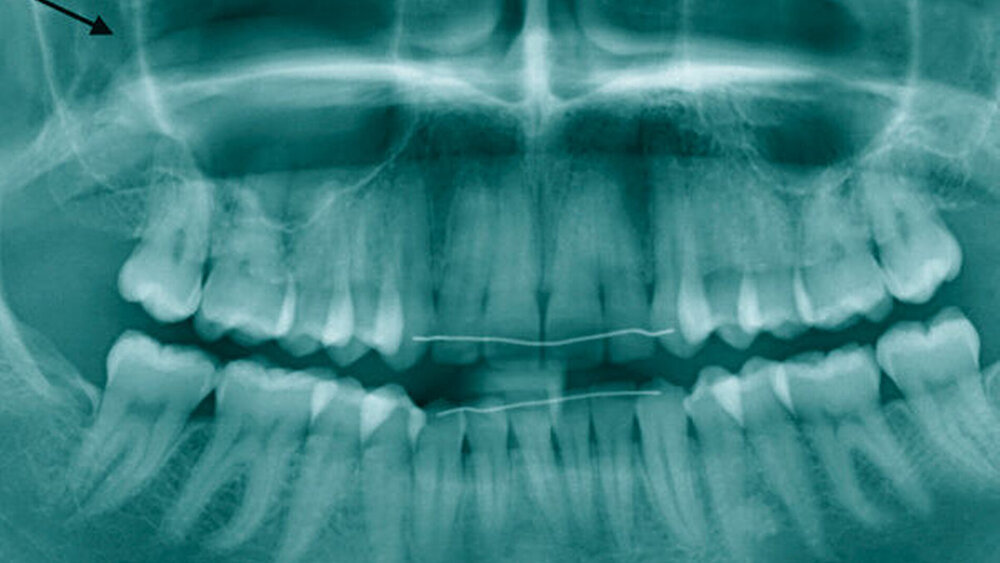

Patientin Nr. 1 hatte sich bereits beim Hauszahnarzt vorgestellt, der anhand eines Orthopantomogramms (OPG, Abbildung 1) die Verdachtsdiagnose einer Mukozele gestellt hatte. Da klinisch und röntgenologisch keine odontogene Ursache erkennbar war, wurde die Patientin erst zum Hals-, Nasen- und Ohrenarzt überwiesen, bevor sie sich in unserer Ambulanz vorstellte. Zu diesem Zeitpunkt beschrieb sie nun vor allem vermehrte Kopfschmerzen.

Dem jungen Patienten Nr. 2 hingegen wurde etwa ein halbes Jahr vor seiner Erstvorstellung in unserer Ambulanz Zahn 16 gezogen. Die palatinale Wurzelspitze brach beim Extraktionsversuch ab, luxierte in der Folge in den Sinus und war über die Alveole nicht mehr erreichbar. Der Patient wurde im Nachgang darüber aufgeklärt und gebeten, sich beim MKG-Chirurgen zur Sanierung vorzustellen. Aufgrund der zunächst ausbleibenden Symptomatik und der blande verheilenden Alveole vereinbarte der Patient zunächst keinen Termin und stellte sich erst in der Folge des progredienten Beschwerdebildes vor. Zu diesem Termin war die Alveole bereits vollständig zugeheilt. Im OPG zeigte sich der Wurzelrest nicht, im Low-dose-CT war er hingegen einwandfrei zu lokalisieren (Abbildung 2).